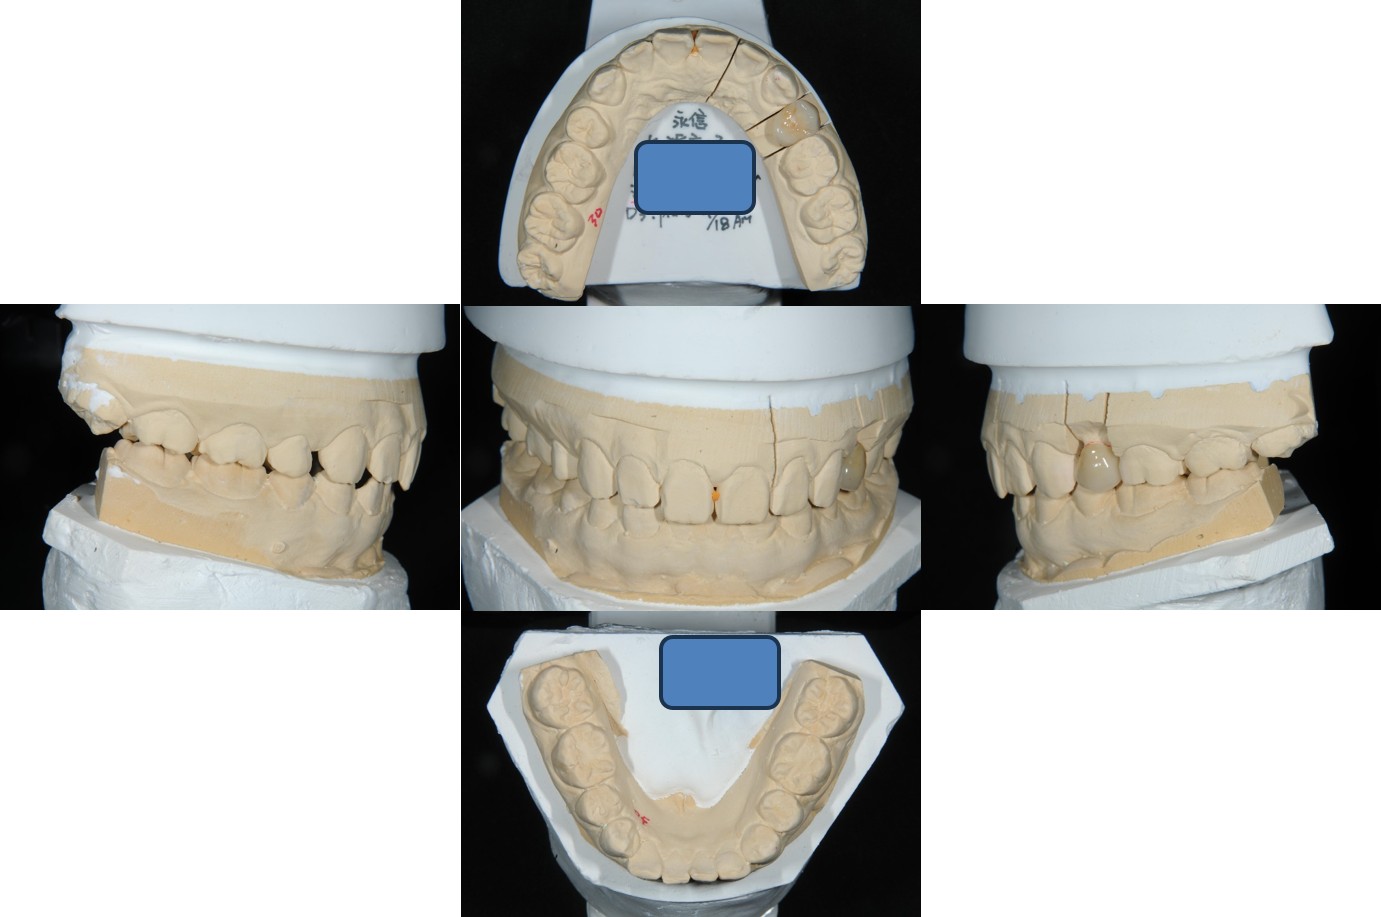

面弓取得、上咬合器

技師於咬合器製作全瓷冠

全鋯冠